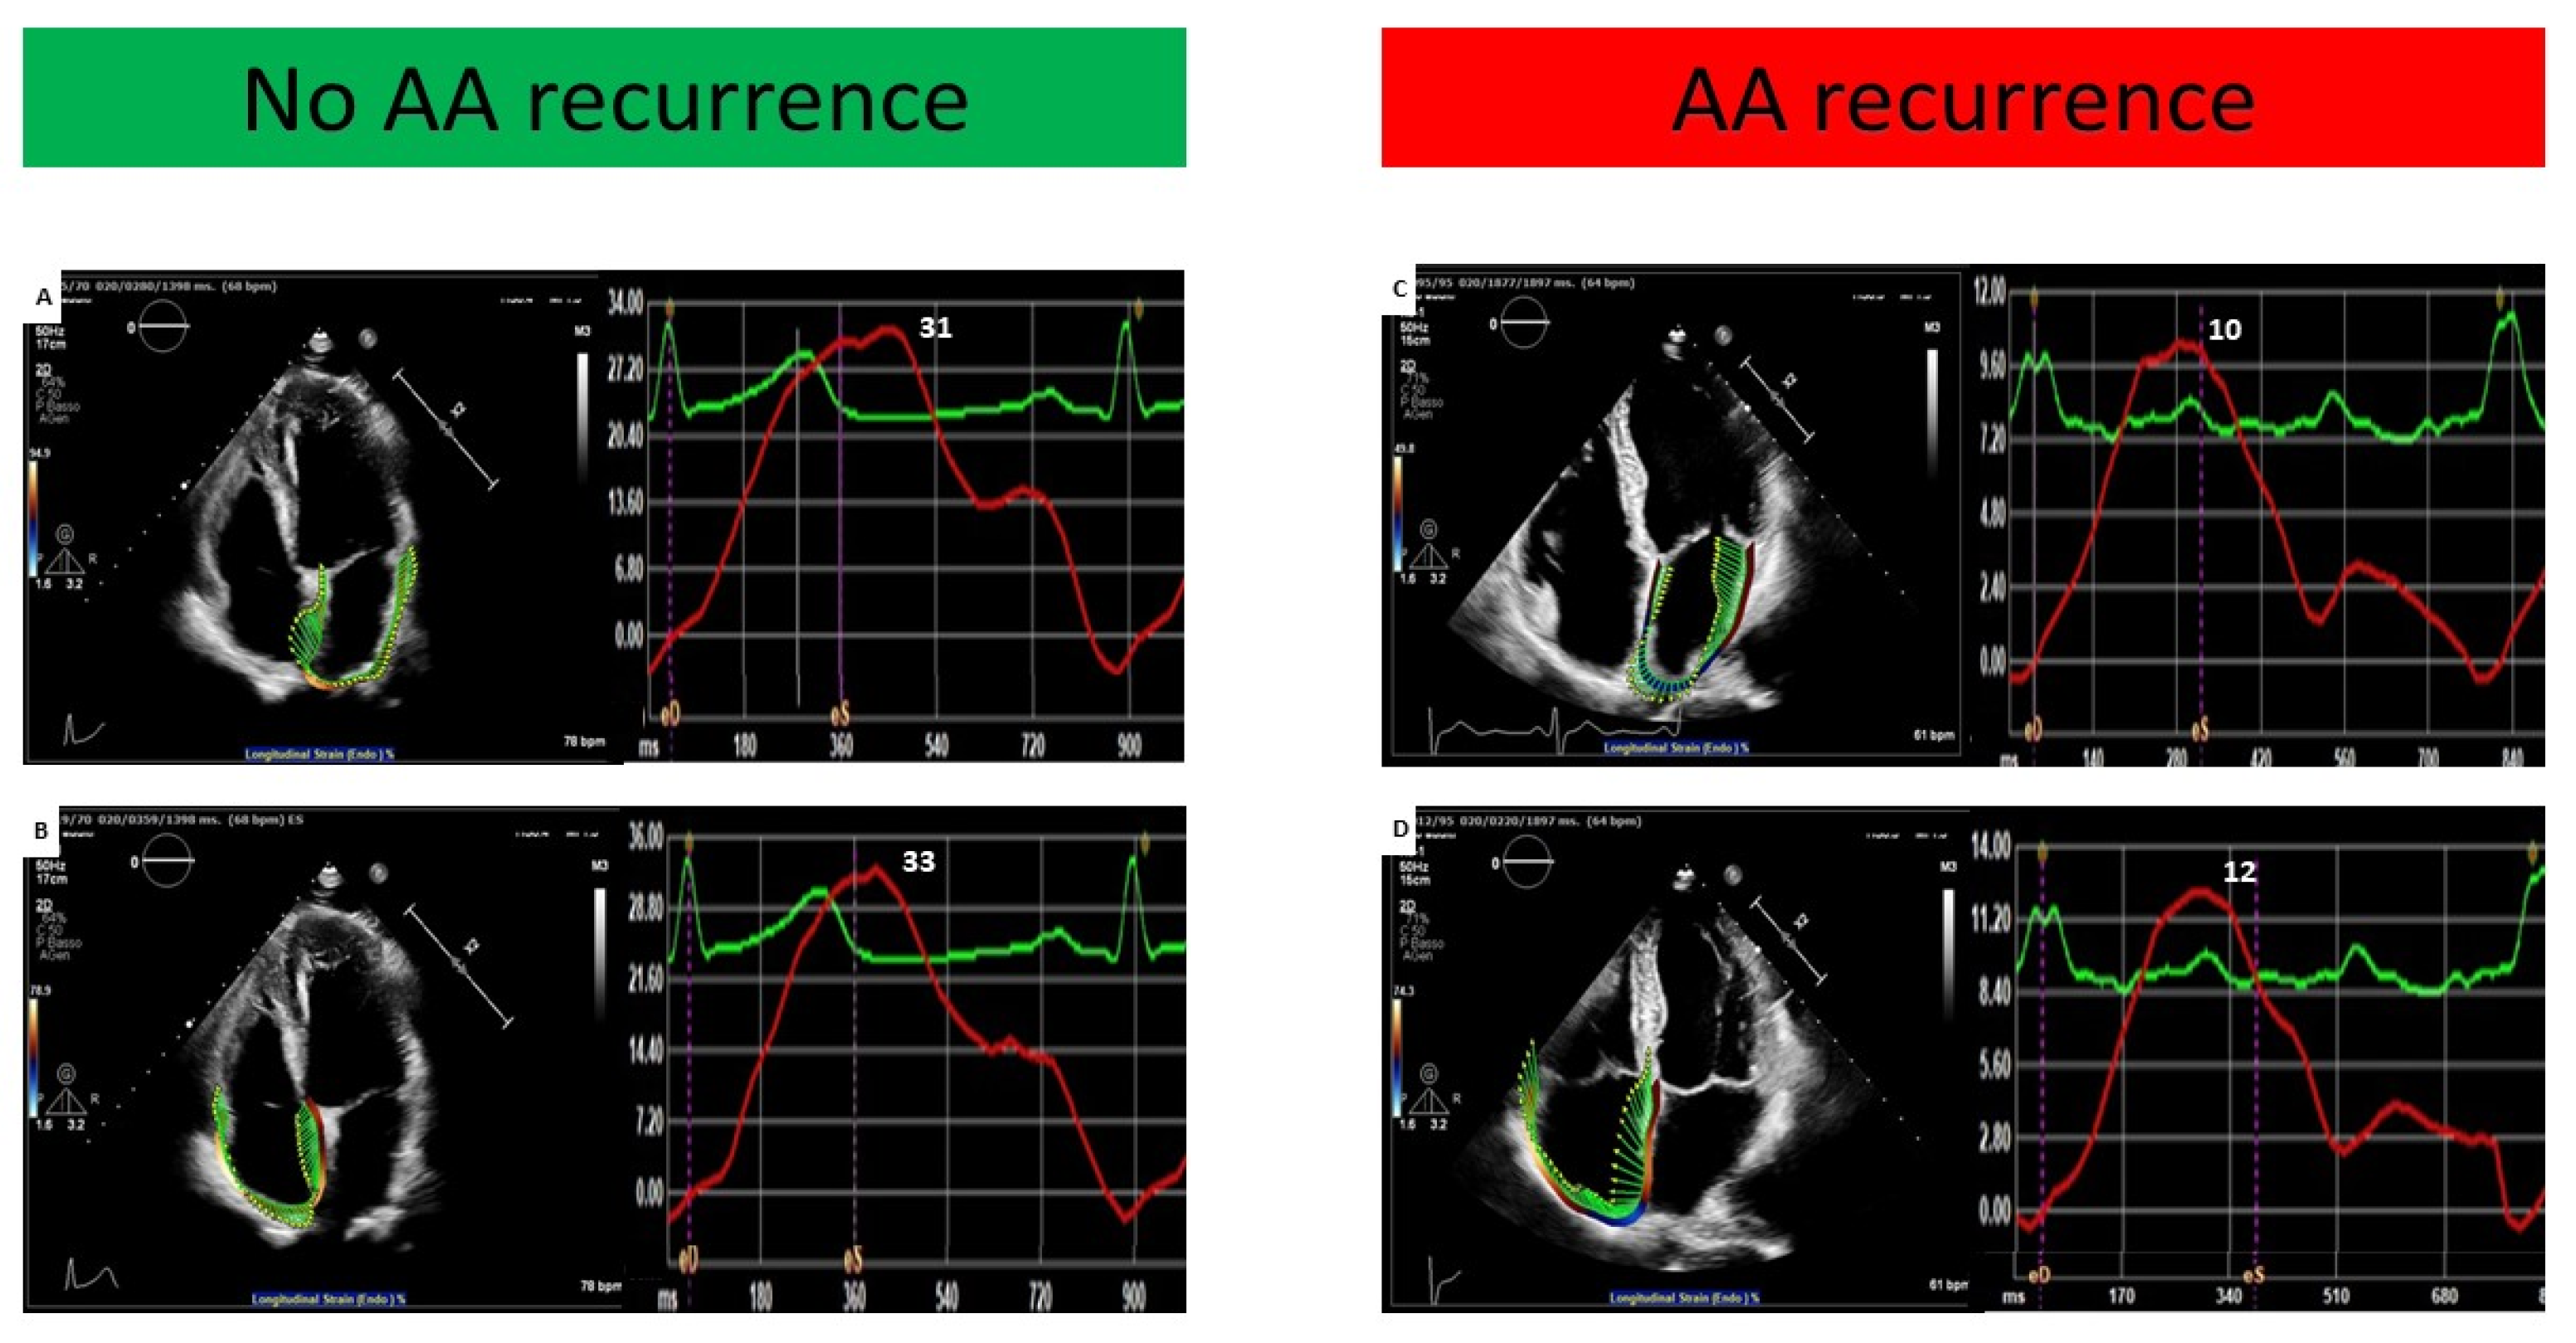

| LASr (%) | 18.8 ± 8.7 | 22.1 ± 8.5 | 13.5 ± 5.2 | <0.001 |

| RASr (%) | 17.6 ± 6.9 | 20.3 ± 6.3 | 12.8 ± 5.3 | <0.001 |